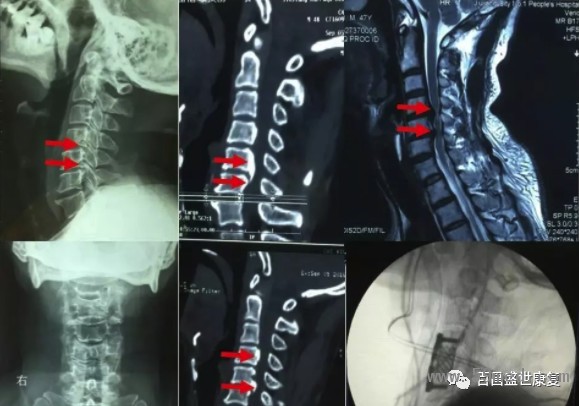

由于該型頸椎病起病隱匿,發(fā)作很緩慢,因此很多患者得不到及早診斷,就診時(shí)候已經(jīng)出現(xiàn)脊髓信號(hào)改變,從而導(dǎo)致不可逆性脊髓損傷。

因此對(duì)于此類型頸椎病患者,但凡有癥狀懷疑此型頸椎病時(shí),早期頸椎核磁共振檢查十分必要,若核磁共振提示脊髓壓迫導(dǎo)致脊髓信號(hào)改變,應(yīng)該盡快實(shí)施手術(shù)。

不同類型頸椎病表現(xiàn)不一樣,也有部分患者為混合上述分型中的一種或者多種類型,也叫混合型頸椎病。不同患者對(duì)疾病耐受程度不一樣,有些患者癥狀很?chē)?yán)重,影像學(xué)檢查卻很輕;部分患者癥狀很輕微,影像學(xué)檢查已經(jīng)出現(xiàn)很?chē)?yán)重的退變和脊髓神經(jīng)壓迫表現(xiàn)。

因此既不能單純根據(jù)癥狀判斷疾病的嚴(yán)重程度,也不能單純根據(jù)影像學(xué)病變確定治療方案。典型的臨床表現(xiàn),結(jié)合科學(xué)的影像學(xué)檢查綜合判斷,有助于確定頸椎病類型和疾病的嚴(yán)重程度,從而選擇合適治療方案。